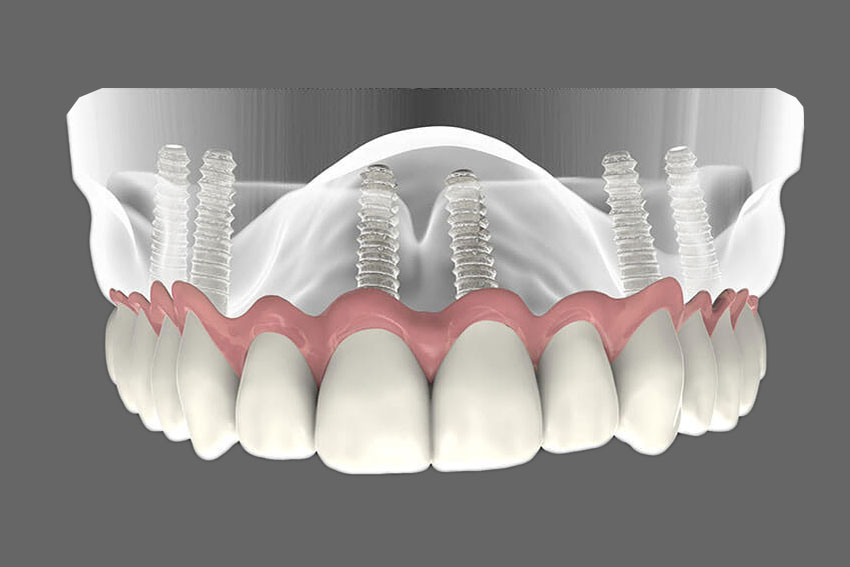

Prosthetic full arch dentures are a popular dental solution for individuals with missing teeth. This article addresses common questions and provides answers to help individuals gain a better understanding of these dentures and their benefits.

- What are Prosthetic full arch dentures? Prosthetic full arch dentures are custom-made dental appliances that replace an entire arch of missing teeth, either in the upper or lower jaw. They provide a functional and aesthetic replacement for missing teeth.

- How are prosthetic full arch dentures different from traditional dentures? Prosthetic full arch dentures replace an entire arch of teeth, while traditional dentures are designed to replace only a few missing teeth. Full arch dentures offer better stability and functionality.